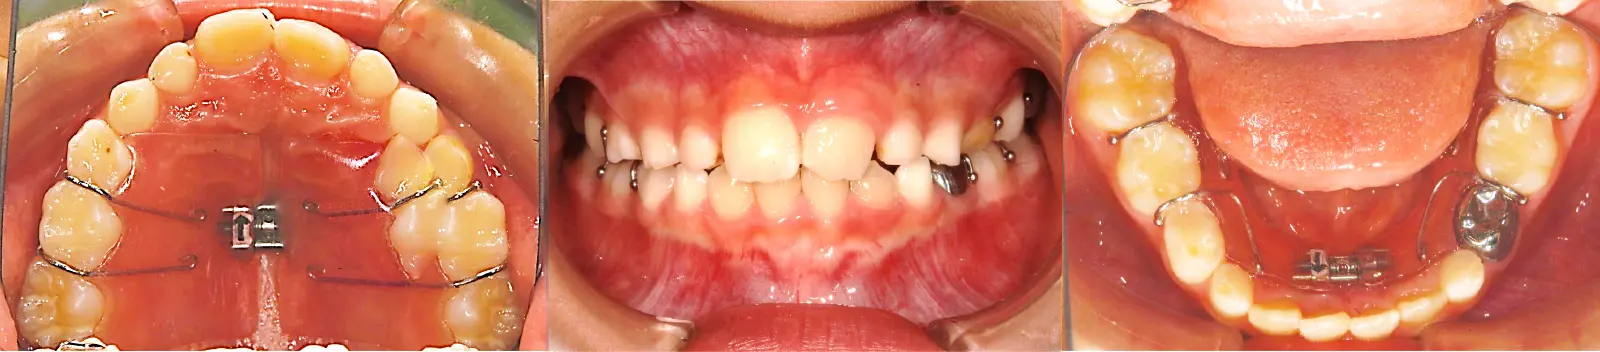

アングルⅠ級 反対咬合

第一段階の治療のみで、

永久歯は問題なく萌出し、安定している

- 主訴

1歯のみの逆破蓋

- 年齢

7歳

- 治療期間

6ヶ月

- 治療回数

6回

- 治療に用いた主な装置

2by2、拡大床

- 治療費

400,000円(税別)トータル料金

- 抜歯部位

非抜歯